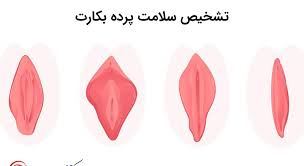

پردهی بکارت یک بافت گوشتی نازک است که در ابتدای ورودی واژن زن قرار دارد. این ورودی شکلهای مختلفی دارد و در بیش از نیمی از خانمها بعد از برقراری رابطهی جنسی و یا ورود یک جسم خارجی به داخل واژن پاره میشود و با یا بدون خونریزی این پارگی را نشان میدهد. از آن جایی که مسئلهی باکرگی در فرهنگها و مذهبهای مختلف تعاریف متنوعی دارد و از نقطهنظرهای مختلفی به این مسئله نگاه میشود، برخی از افرادی که علارغم باورها و اعتقادات مذهبی و عرفیشان، رابطهی جنسی داشتهاند و دچار پارگی پردهی بکارت شدهاند، با مشکل مواجه شدهاند و به ترمیم پردهی بکارت فکر میکنند.

پرده بکارت یک غشای ظریف است که در دهانه واژن دختران قرار دارد و از عفونت جلوگیری می کند.

عوامل موثر بر پارگی پرده بکارت

پارگی پرده بکارت اغلب در نتیجه ورود جسم خارجی به رگ یا ضربه سنگین به آن ناحیه است.

در این حالت ممکن است فرد دچار درد یا خونریزی شود. با توجه به انواع مختلف مدل های غشایی ظروف، آسیب های ناشی از آن نیز می تواند انواع مختلفی داشته باشد.